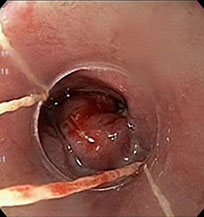

Lesión de Dieulafoy

Es una anomalía vascular localizada generalmente en estómago proximal y consiste en la presencia de una arteria de gran calibre en la submucosa y ocasionalmente en la mucosa, aunque el diagnóstico definitivo es anatomopatológico, con la endoscopia se puede alcanzar una precisión elevada.